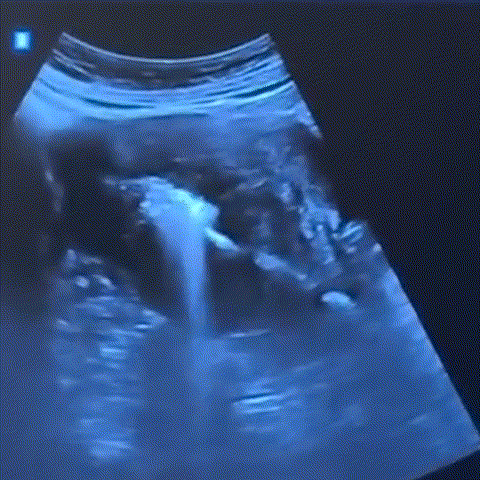

실시간 초음파 상담

화면을 보며 직접 확인

고해상도 초음파를 통해 병변의 위치와 깊이를 실시간으로 파악합니다.

모니터를 함께 보며 현재 상태를 명확히 설명해 드립니다.